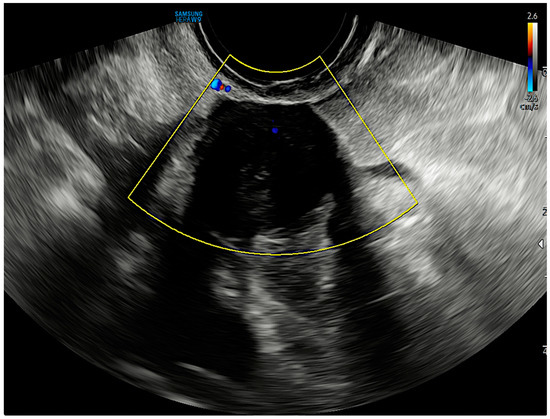

2. Case Report